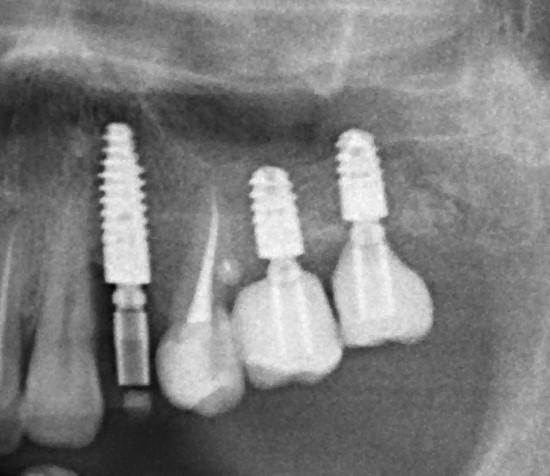

Имплантация и остеопластика: вместе или врозь? Часть II плюс Ankylos, плюс Geistlich